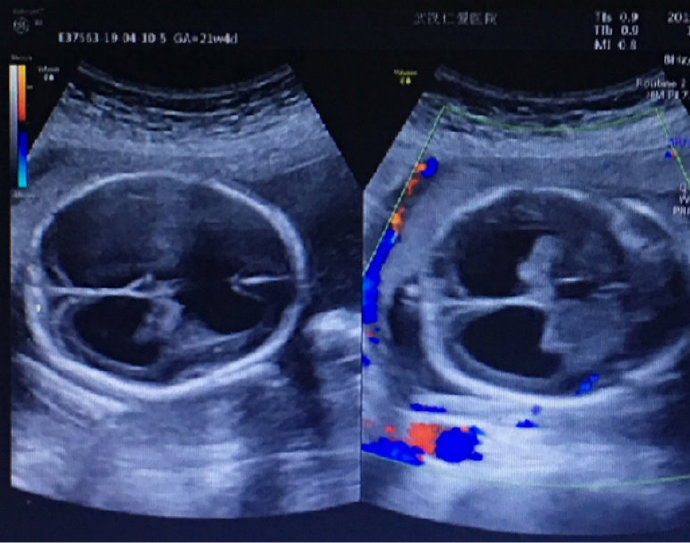

懷孕期間是每個(gè)女人一生中最重要的時(shí)期,可是有些孕婦懷孕期間亂用藥卻導(dǎo)致終生遺憾。最近武漢就有一名孕婦,在孕早期因感冒、胃疼亂吃了很多消炎和止痛藥,結(jié)果在孕22周···